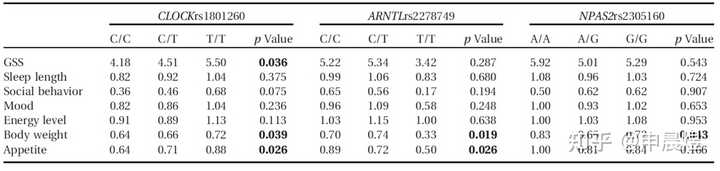

生物钟的基因多态性与情绪障碍密切相关

Clock基因的rs1801260多态性位点、NPAS2 基因的rs2305160 多态性位点和ARNTL 基因的rs2278749 多态性位点与季节性的情绪障碍及行为活动(体重以及食欲变化等)有关[6]。